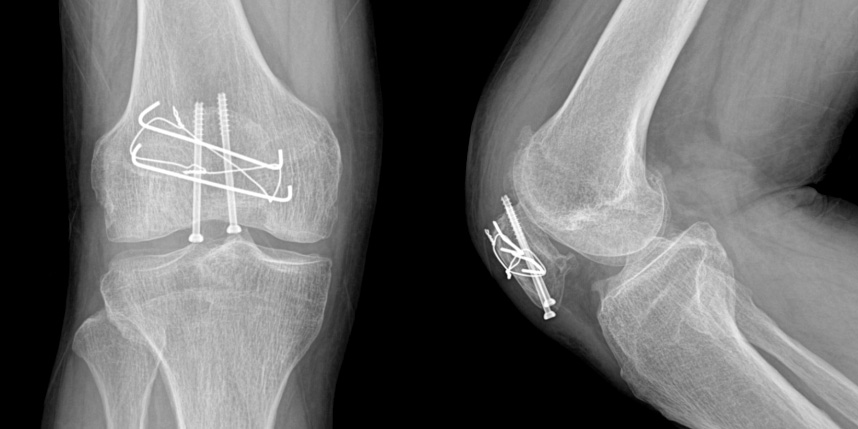

골절은 정확하게 골절편을 잘 맞추고 고정하는 것이 중요합니다. 특히 관절면을 잘 맞추는 것이 중요합니다.

무릎 골절